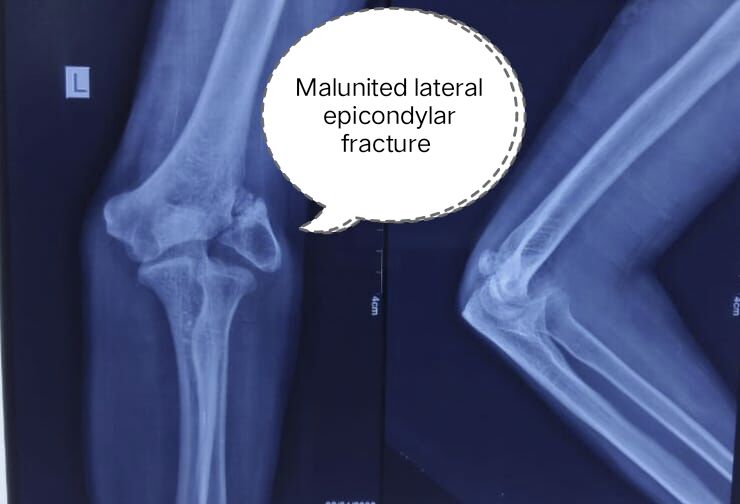

He was a young male who had suffered an elbow injury years ago. At that time, the fracture around his lateral epicondyle had healed improperly, forming a malunion. He ignored it, thinking the pain was gone and the problem was over.

On examination, it became clear that he had developed Tardy Ulnar Nerve Palsy – a delayed complication caused by the malunited fracture pressing on the ulnar nerve at the elbow.